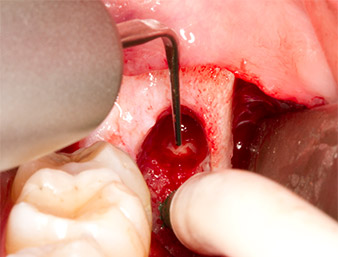

The same activated instrument was inserted into the root canal and loosened the fragment as a result of its micro-oscillating vibrations (Fig. 9, 10).

Piezomed P1

Fig. 10: Due to its slender shape, the instrument can penetrate the root canal and remove the root remnant by means of micro-oscillation (vibration).

It was then possible to remove the approximately six-millimetre-long root remnant in one piece with the P1 attachment (Fig. 11).